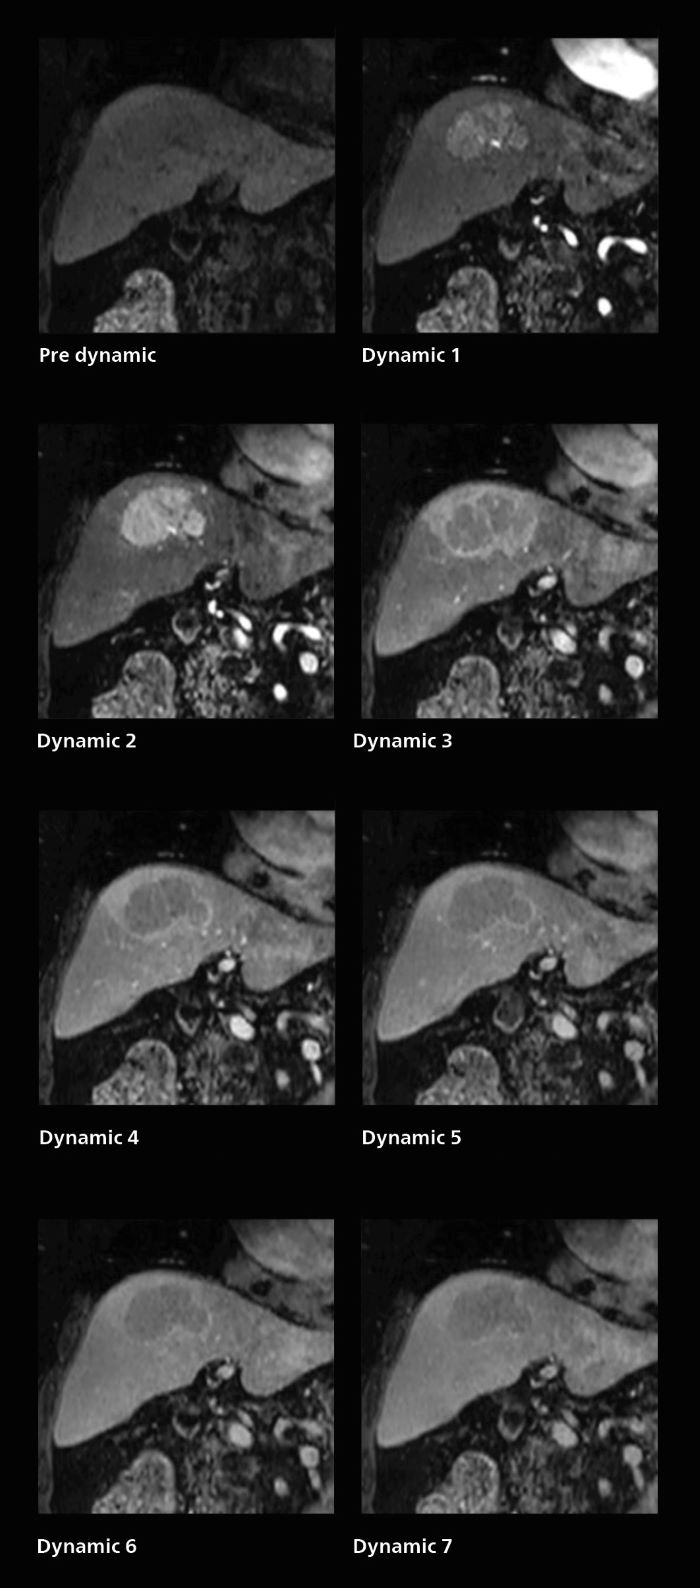

Rapid clarity for stroke and liver

Dynamic MRI of liver using SmartSpeed

A patient was referred for MR imaging of HCC. A double arterial volume dynamic study was performed. Since it is a volume dynamic study, it can also be evaluated using MPR images. Performed on Elition X.

The hospital’s routine ExamCard for dynamic MRI of the liver uses total scan duration 1:05 min, dynamic scan time 9.2 sec, 1.6 x 1.8 x 2.0 mm, 200 slices, acceleration factor 8.